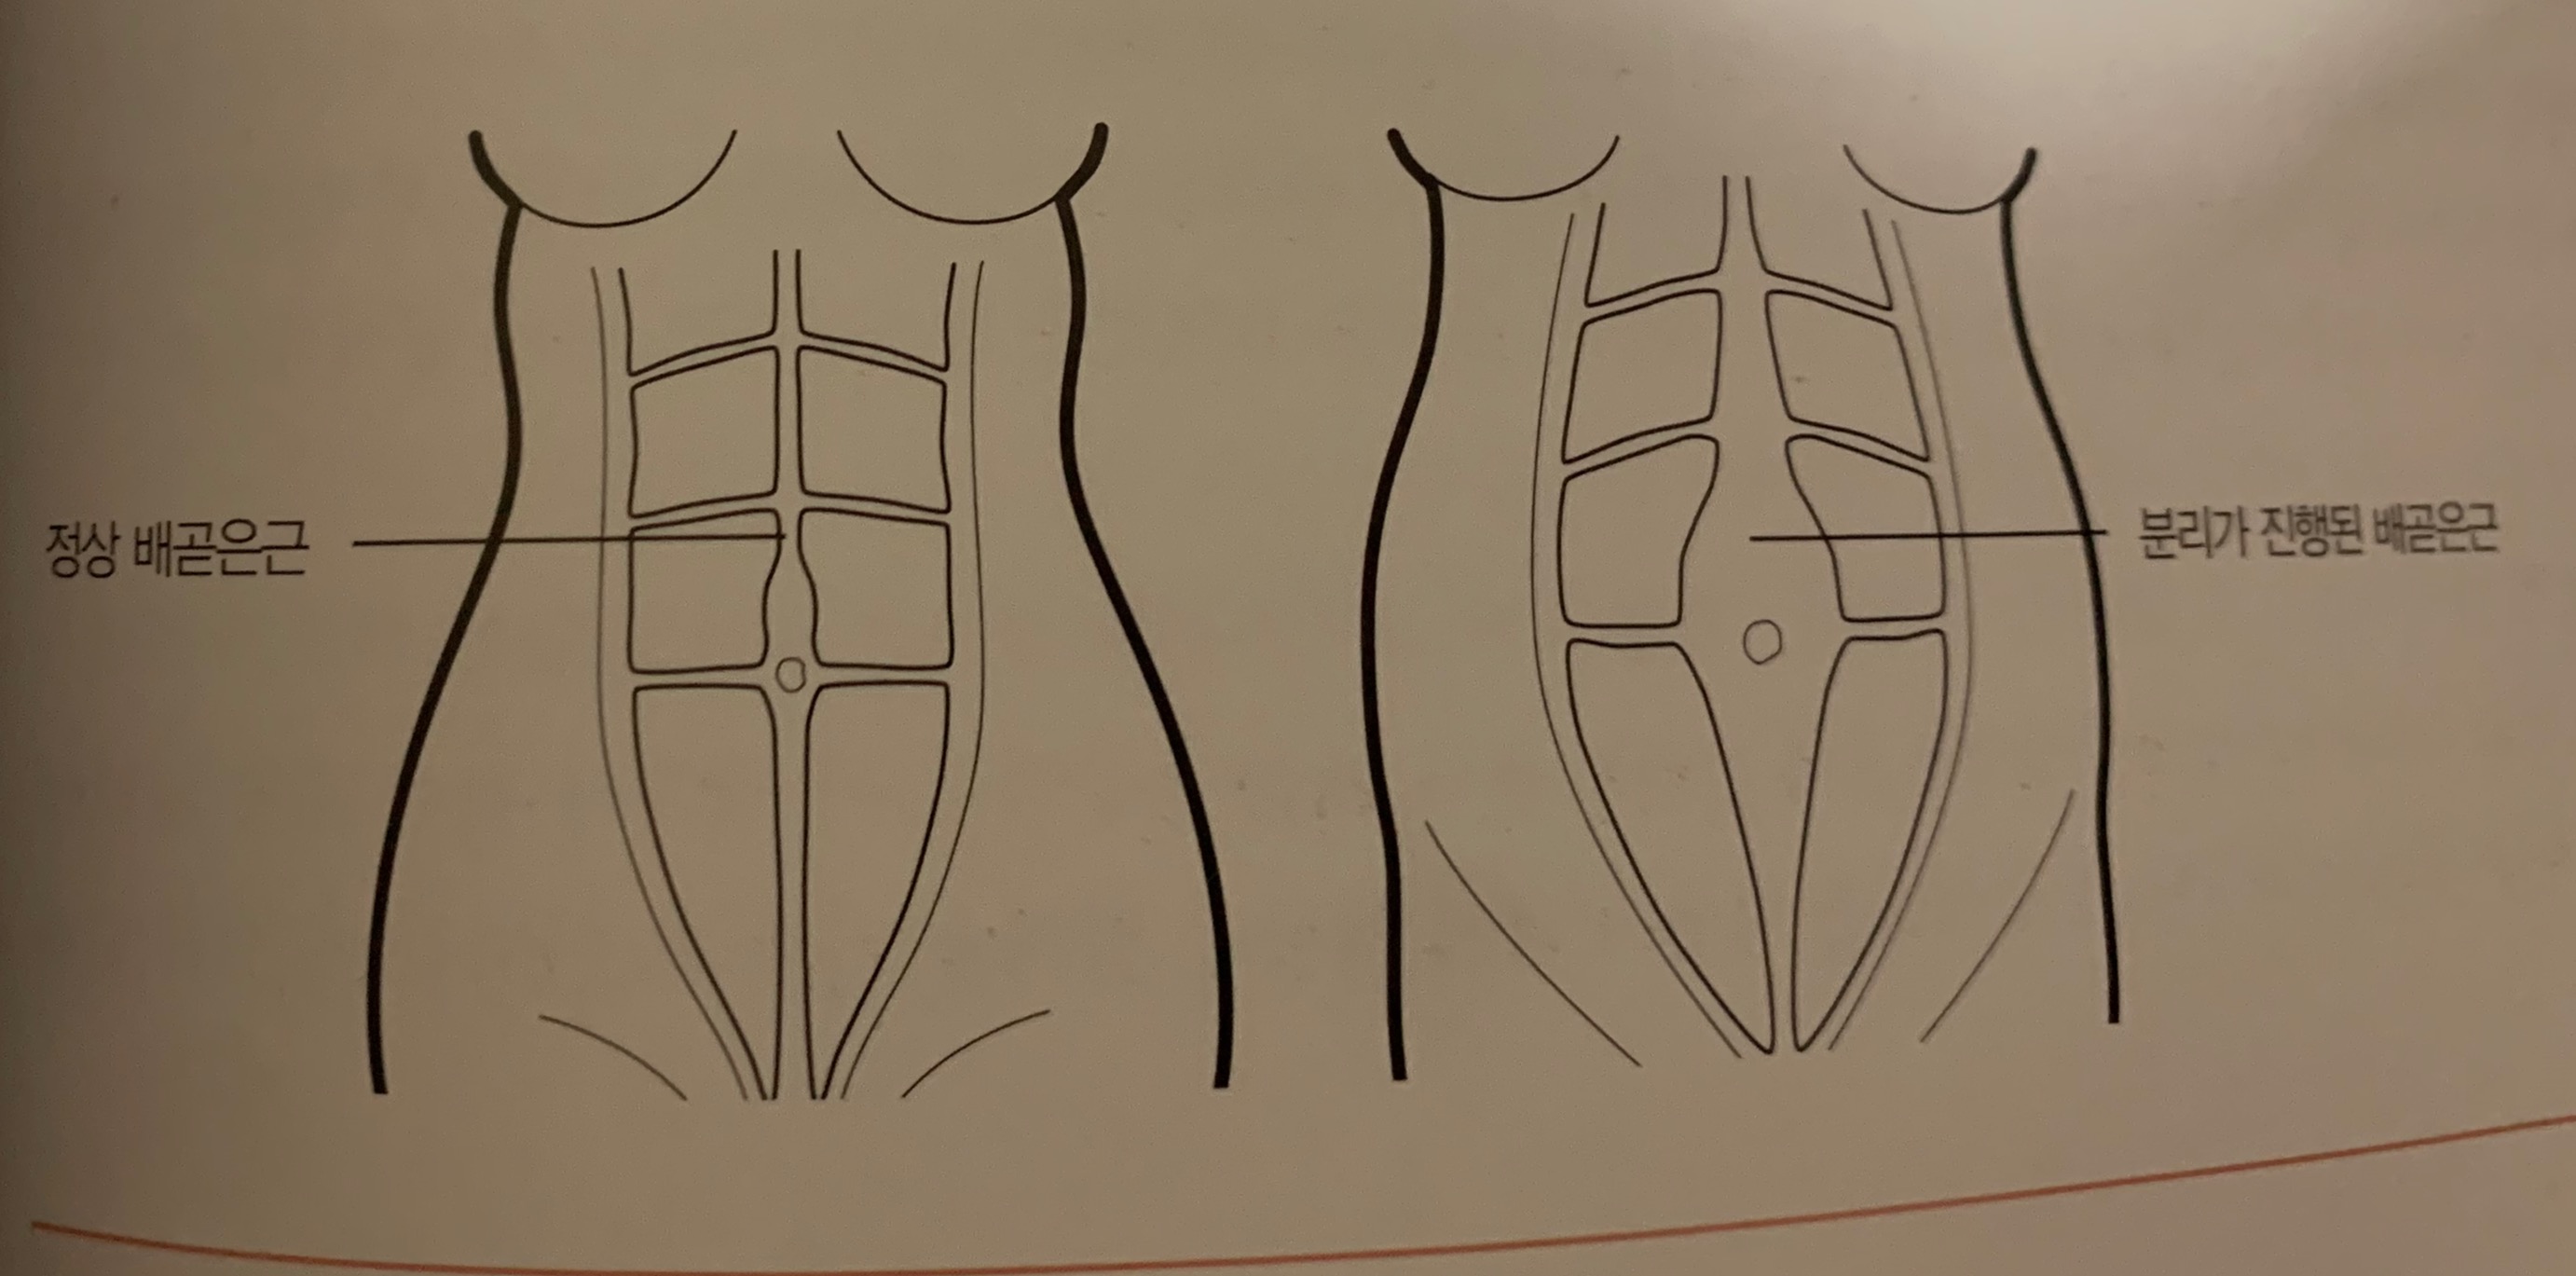

12. 배곧은근 분리( = 복직근 이개)(추후에 더 자세하게 설명하겠습니다.)

-> 임신 중기부터 배가 불러지면서 배곧은근의 힘줄 부분이 벌어지게 된다

임신 중기에는 30프로 이상 발생하며, 임신후기에는 60프로 이상 발생한다.

운동으로 인해 35프로 정도 줄일 수 있다. 단, 과도한 복부운동은 삼가해주세요